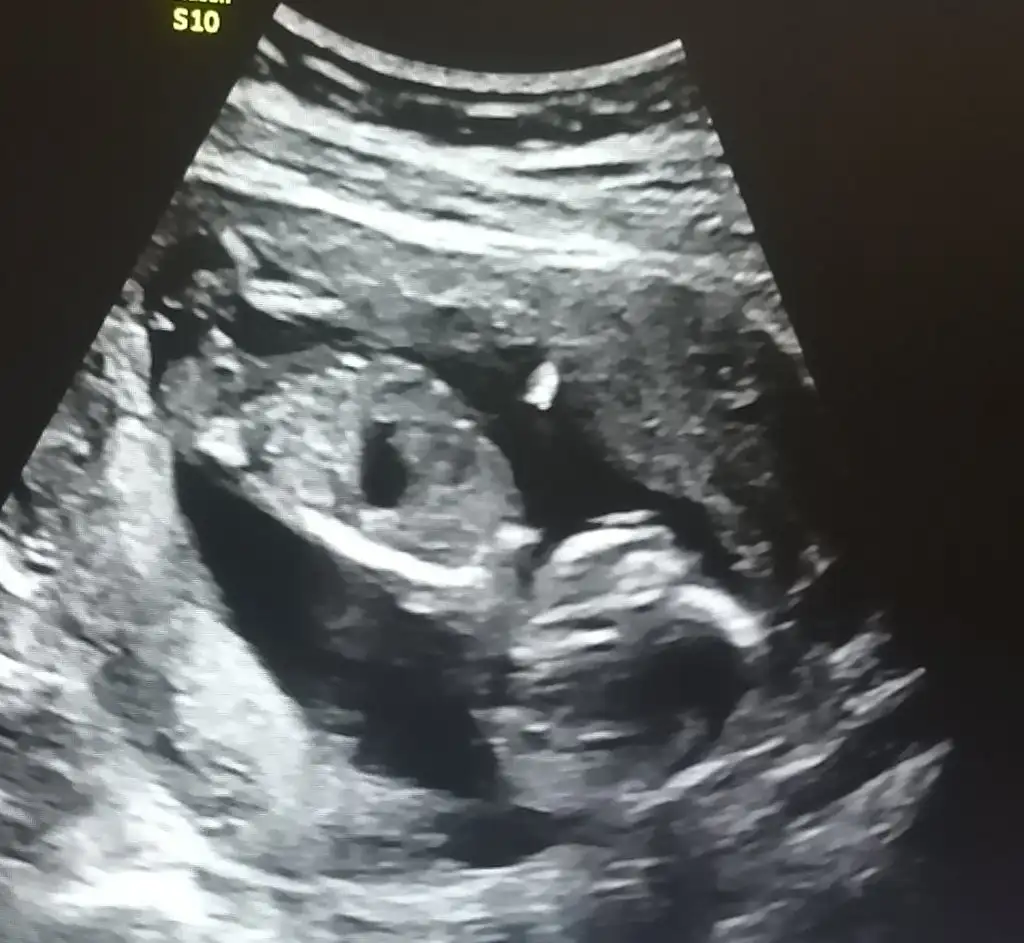

Nuba göre :) benimki kızdı tuttu . Bence seninki de tutacak . Öğrenince haber ver muhakkakCanım neye gore erkek dedin

Nuba göre :) benimki kızdı tuttu . Bence seninki de tutacak . Öğrenince haber ver muhakkak

Tamam canimmNuba göre :) benimki kızdı tuttu . Bence seninki de tutacak . Öğrenince haber ver muhakkak